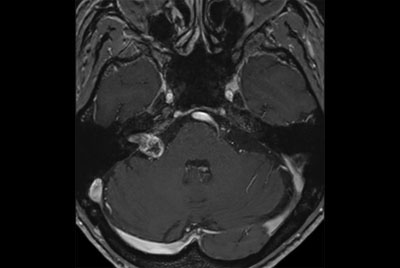

Cervical Spine - Cord lesion